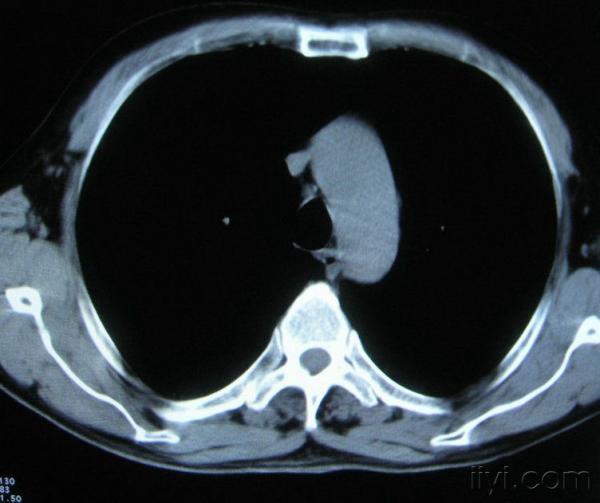

男。60岁,胸片示支气管炎治疗后复查CT。

你指那个肯定是淋巴结,中央系坏死,这很常见,特别在双侧腹股沟会经常看到。这个双侧腋窝及纵隔见多发小淋巴结征。

根据位置考虑应该是淋巴结,密度不均,是因为肿大的淋巴结中心液化坏死